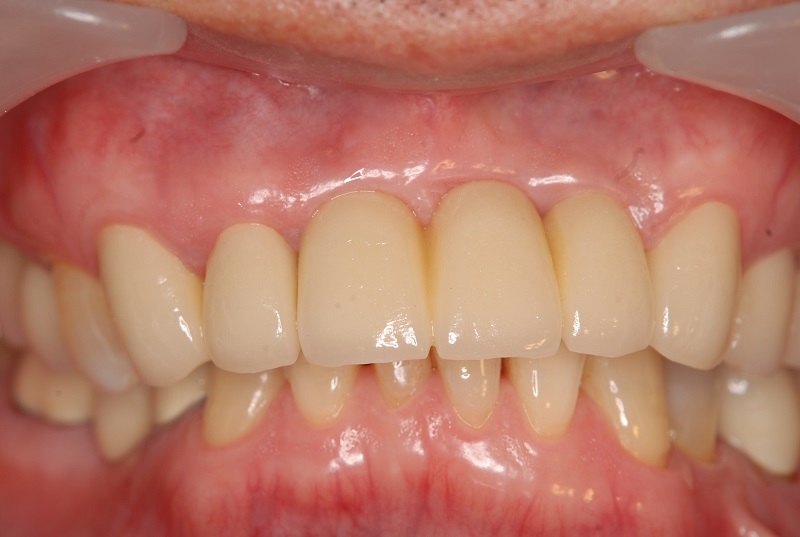

症例2【70代女性】主訴 義歯がわずらわしい・しっかり噛みたい

治療前

治療後(2年経過)

※説明

主訴 上顎のみ部分義歯を使用しているが、入れ歯が煩わしい、固定制のインプラントにして欲しいと来院。

左右上顎第一大臼歯相当は、骨の高さが不足しており、ソケットリフト(骨造成)の必要があり、左右第一小臼歯、第一大臼歯支台のインプラントブリッジを提案。

採血で得られた、CGFメンブレンとAFGブロック(人工骨β‐TCPとAFGを混ぜたブロック)を使用し骨を挙上し、インプラントを埋入。

右下のブリッジも、短根歯で動揺が激しい為に抜歯し、インプラント埋入。

上顎の免荷期間は約4ヶ月、下顎の免荷期間は約2ヶ月を経て、仮歯を装着、リハビリをし、メタルボンド(金属焼付ポーセレン)を装着。

費用 280万(オペ・ソケットリフト・人工骨・採血による濃縮血小板生成・仮歯・最終補綴物まで含む)